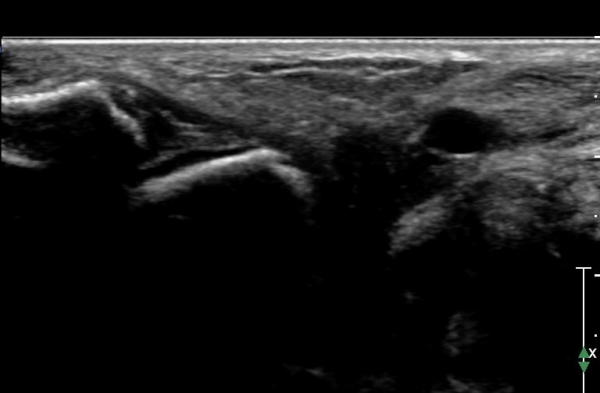

Àü°ÅºñÀδë ÇϺΠÁ¾´Ü¸é°Ë»ç¿¡¼­ Àü°ÅºñÀδëÀÇ Àú¿¡ÄÚ À§Ãø°ú Á·±Ùµ¿ÀÇ ¼ö¾×Àú·ù°¡

°üÂûµÈ´Ù(»çÁø 2, 3, 4).